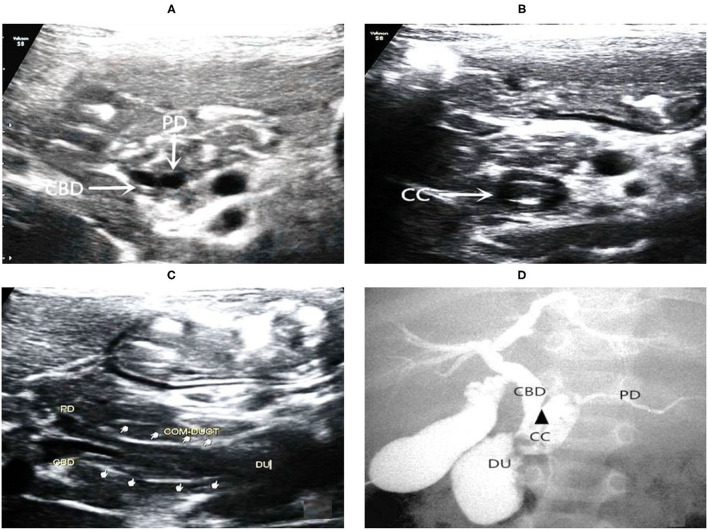

On the basis of the new JSPBM’s classification, the individual morphologic features of PBM were described as four types (ref. 11) in presenting our ultrasound report: type A (stenotic)—the distal CBD with stenosis before joining with the CC, and an angle of slightly < 90° usually observed in the conjunction between PD and CBD at a site distant from the papilla of Vater; type B (non-stenotic)—the distal CBD emerging but without stenosis pattern before joining with the CC, in addition, an approximately right angle customarily seen in the conjunction between PD and CBD at a site distant from the papilla; type C (dilated channel)—the dilated CC significantly occurred; type D (complex)—a complicated configuration in PBJ contexture including the PD, the terminal portion of the CBD, and the dilated accessory PD, and one end opening as a small nipple in the duodenum and the other end converged with the CBD downward into the CC. Figures 1–4 show the representative imagines of A, B, C, and D types of PBM, respectively.

Among the 31 cases, 14 cases were stenotic type (A), 11 cased were non-stenotic (B), and five were dilated channel (C). The complex type (D) rarely occurred and only one case was found in our medical center. Table 3 shows the comparison among A, B, and C types in terms of gender, age, the maximum internal diameter of CBD, the internal diameter of CC, the length of CC, the internal diameter of the main PD, and the thickness of the gallbladder. Type A causes a significant increase in the internal diameter of CBD. Type C appears significant increases in internal diameter and length of CC and internal diameter of PD.